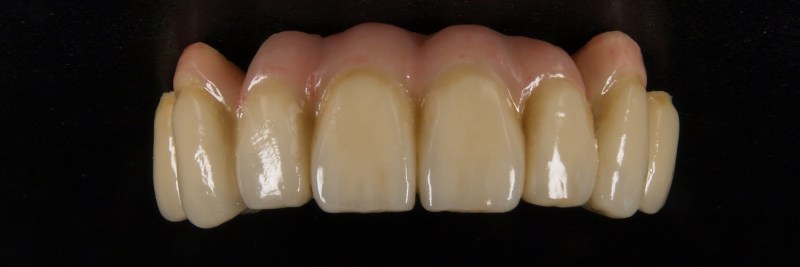

Meisterarbeit von Peter Dengel